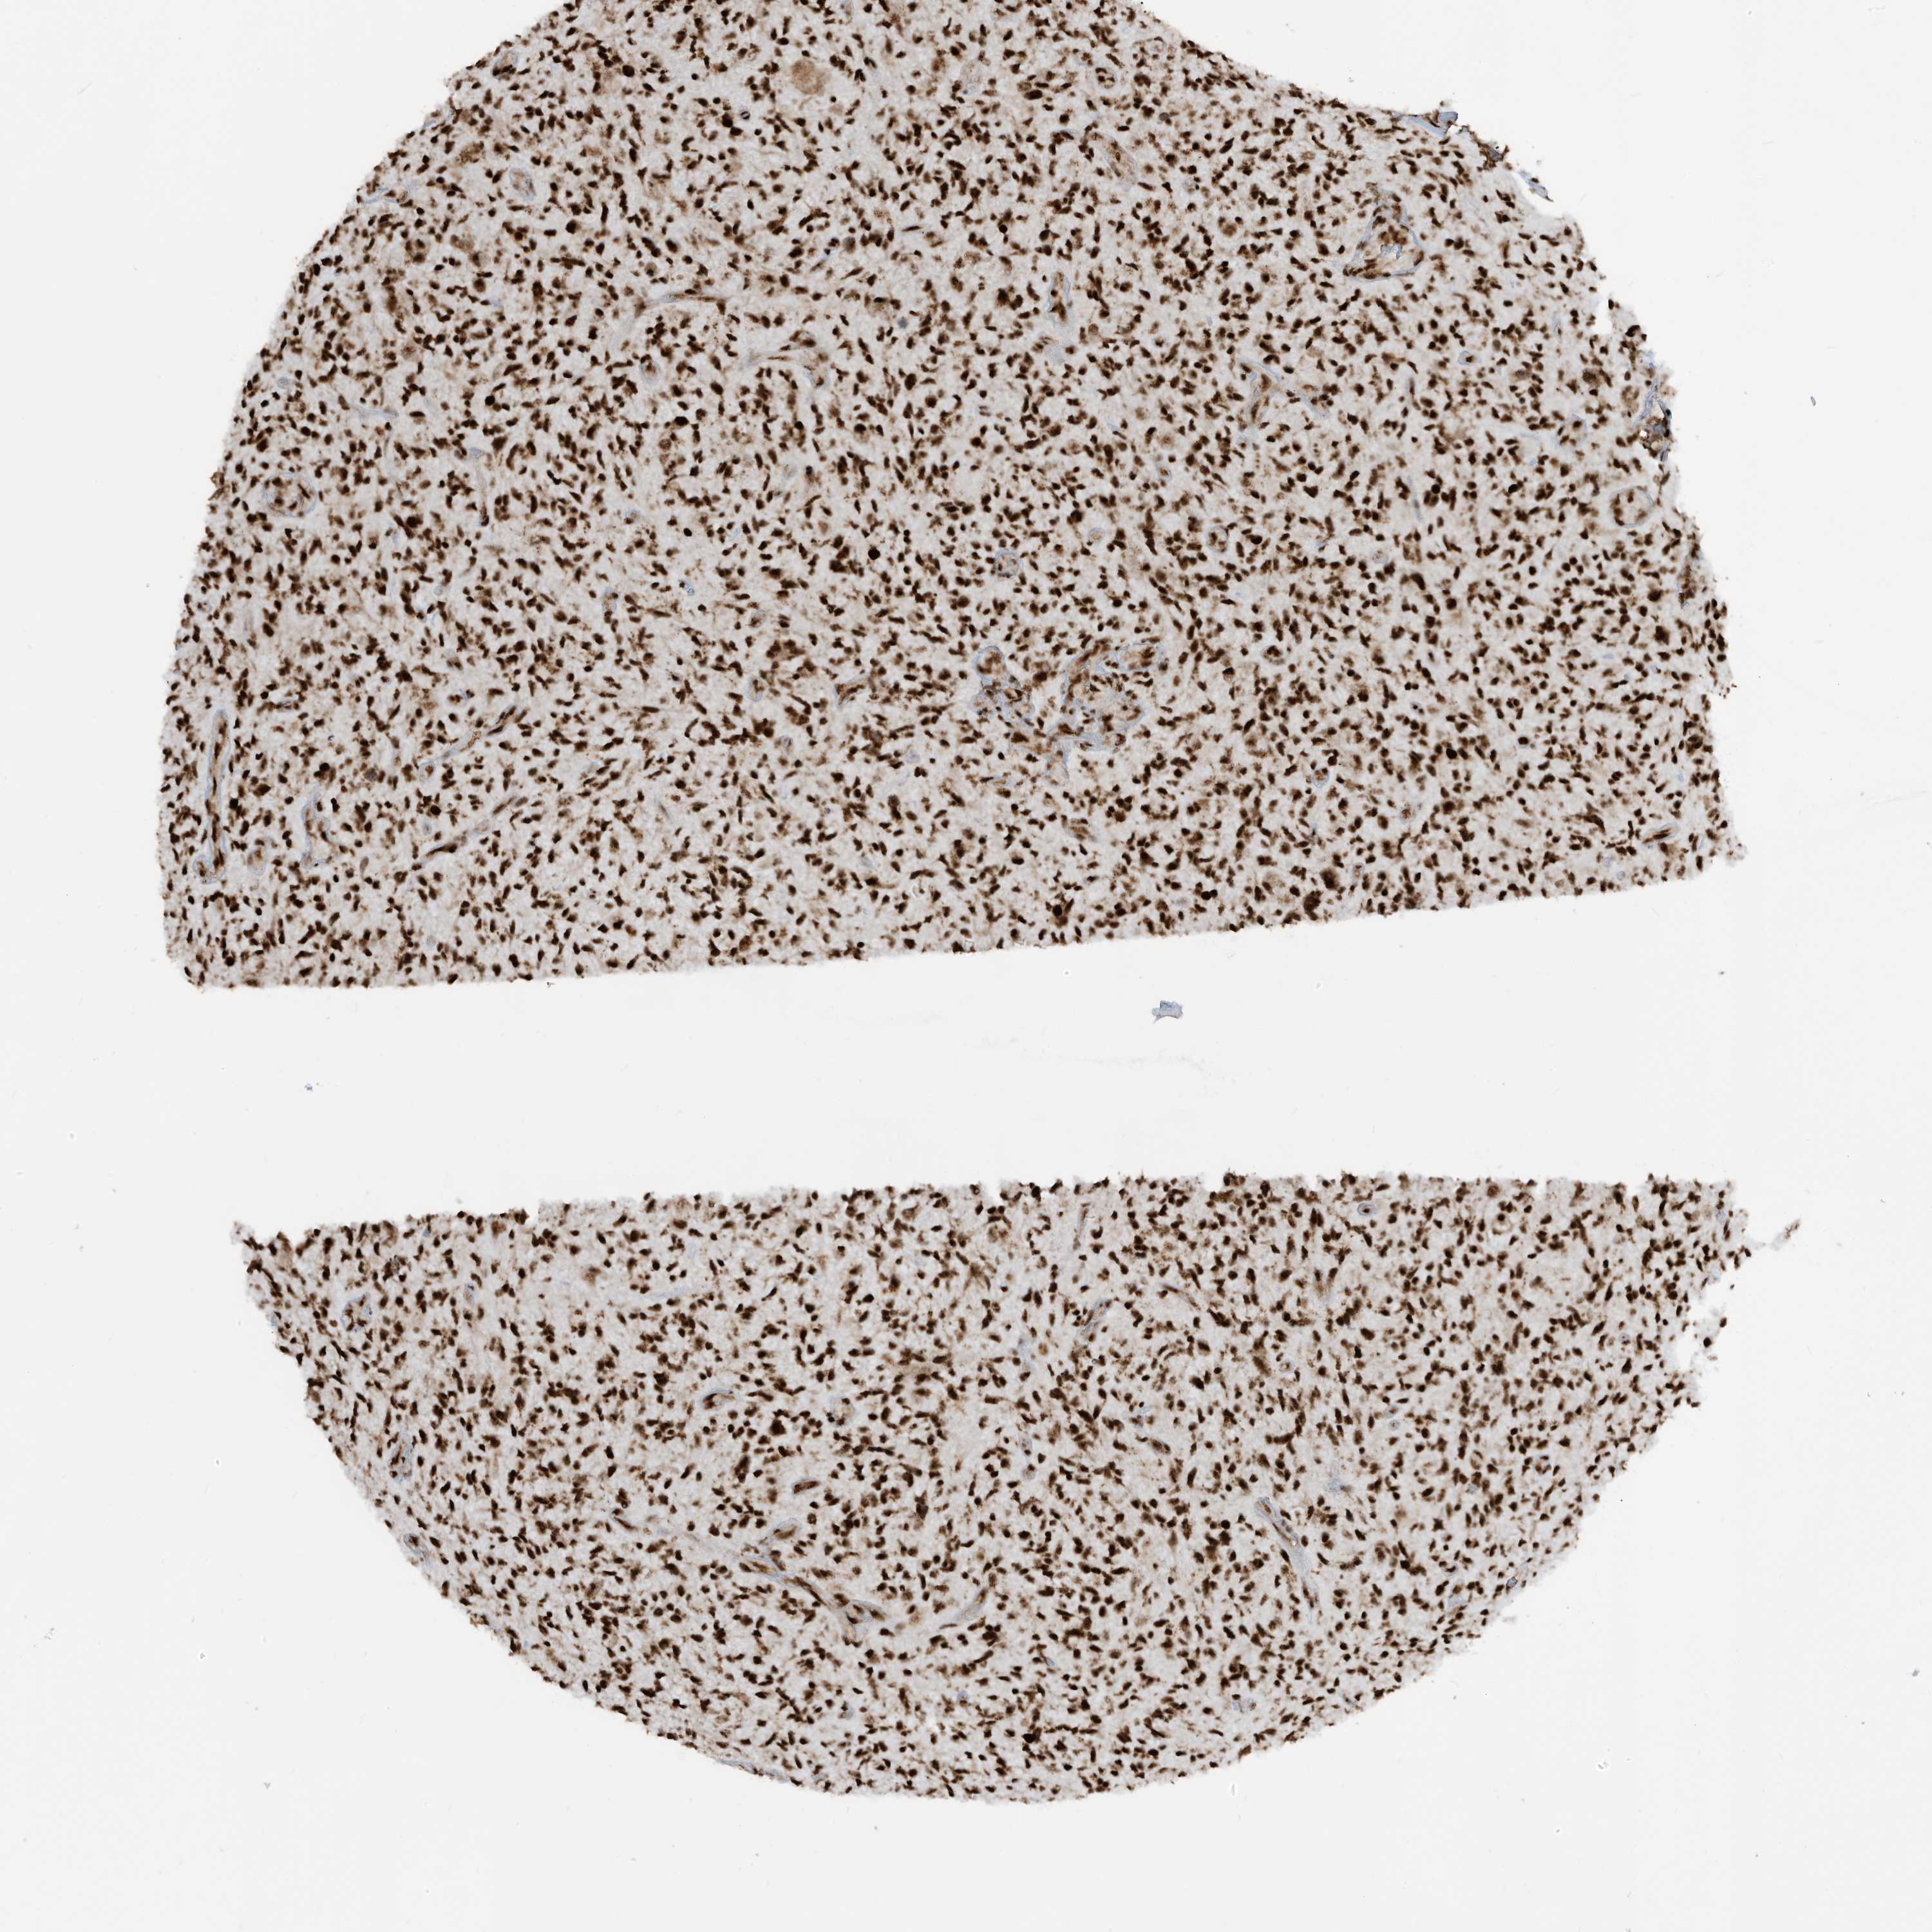

GLIOMA - Protein expressioni

A mouse-over function shows sample information and annotation data. Click on an image to view it in a full screen mode. Samples can be filtered based on level of antibody staining by selecting one or several of the following categories: high, medium, low and not detected. The assay and annotation is described here.

Note that samples used for immunohistochemistry by the Human Protein Atlas do not correspond to samples in the TCGA dataset.

Antibody stainingi

Antibody staining in the annotated cell types in the current human tissue is reported as not detected, low, medium, or high, based on conventional immunohistochemistry profiling in selected tissues. This score is based on the combination of the staining intensity and fraction of stained cells.

Each image is clickable and will lead to virtual microscopy that enables deeper exploration of all samples and also displays staining intensity scores, fraction scores and subcellular localization as well as patient and tissue information for each sample.

Antibody HPA034669

Staining

High

Medium

Low

Not detected

Intensity

Strong

Moderate

Weak

Negative

Quantity

>75%

75%-25%

<25%

None

Location

Nuclear

Cytoplasmic/membranous

Cytoplasmic/membranous,nuclear

Glioma, malignant, Low grade

Glioma, malignant, High grade

Glioblastoma, NOS